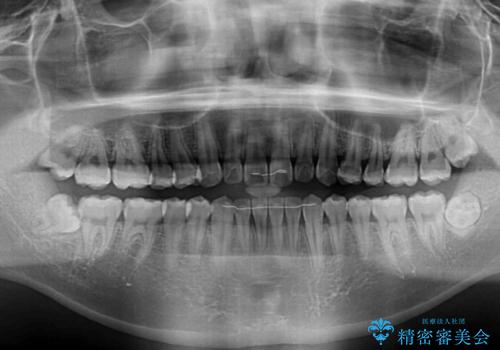

- 上下前歯の叢生を気にして来院された患者様です。

費用を抑え、期間もあまりかけずに治療をしたいとのことで、インビザライン・ライトを用いて矯正治療を行うこととしました。

インビザライン・ライトは、製作できるアライナーの枚数に制限があるため、移動可能な量に限りがあります。

一方で、半年から1年程度で治療を終えることができるため、軽度の歯列不正の患者様には大変お勧めです。